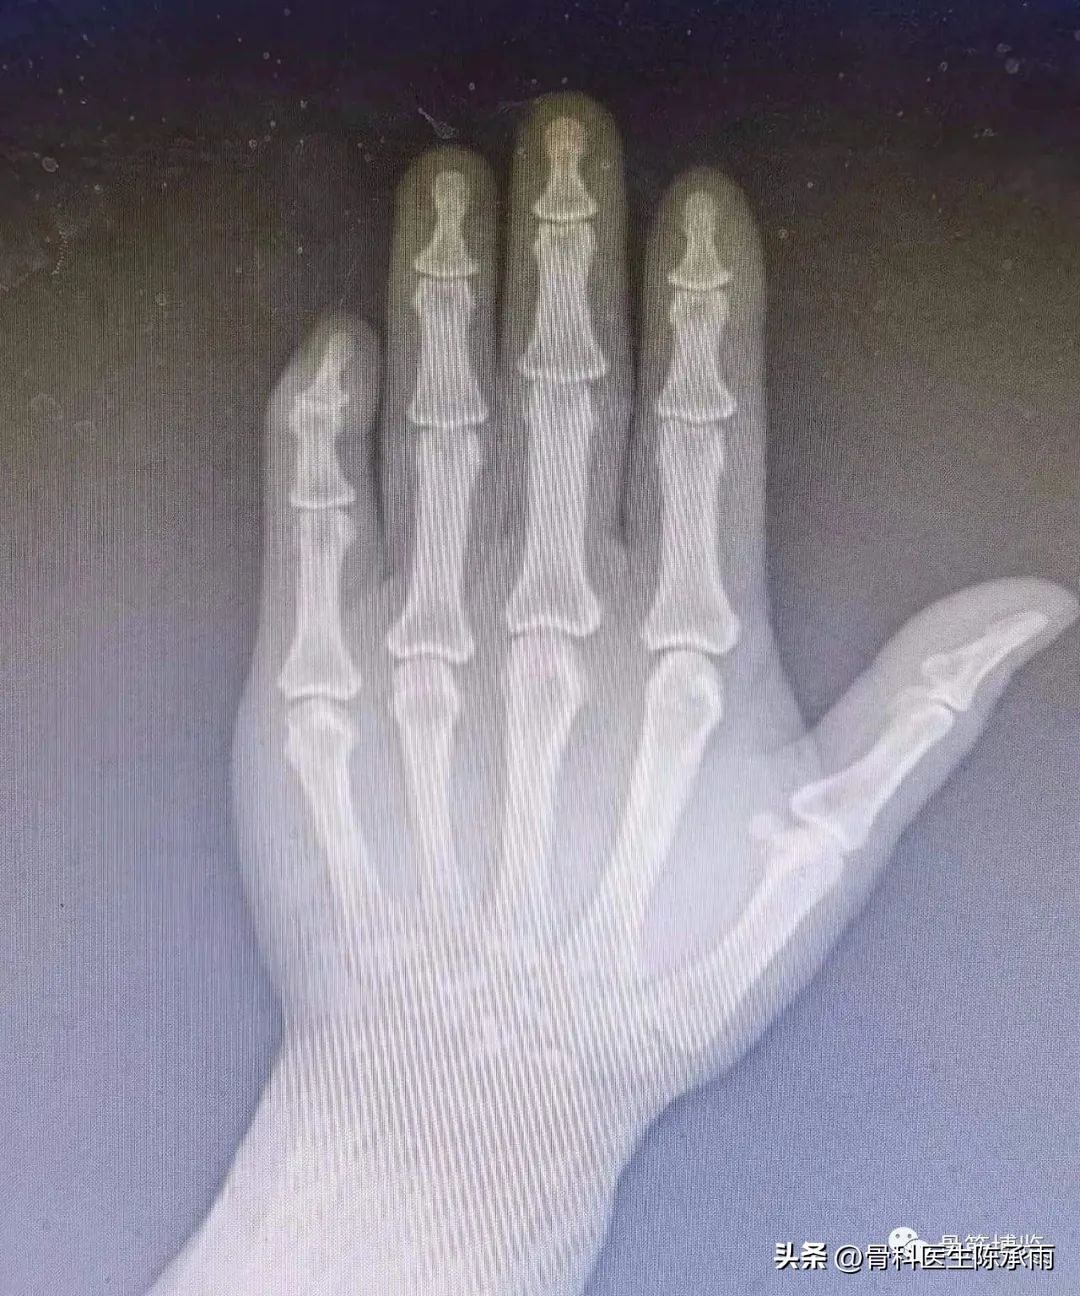

1、Wehbe´ and Schneider 根据侧位X线片表现分型

- I:远侧指间关节无半脱位

- II:有半脱位

- III:有干骺端和骨干的损伤

2、根据骨折块大小分:

- a:小于1/3关节面

- b:1/3-2/3关节面

- c:大于2/3关节面